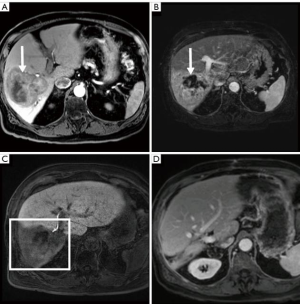

Liver volumetrics and growth kinetics have been used as surrogates of post-operative liver function, but the variability of a patient’s hepatic substrate is not completely captured by these indirect measures of physiology. Liver volumetrics may be prone to additional error in patients with underlying liver disease and previous systemic therapy. It is known that PVE and ALLPS reduce FRS hepatic function however, pre-operative devitalization of the FRS is not achieved with either of these techniques and liver failure remains a major associated morbidity and mortality. TARE induced devitalization of the FRS may represent a more accurate surrogate for post resection liver function as the patient is not physiologically relying on the FRS at the time of surgery (Figures 2,3). This is supported by the low incidence of PHLF in our cohort (3.8%). Conceptually, growth metrics such as DH and KGR may be less informative of the risk of PHLF in the setting of a devitalized FRS as the liver may not hypertrophy beyond what is adequate for the individual patient.

Although FLR hypertrophy is generally slower after TARE than PVE, the high rates of tumor response observed in this study allowed for extended hypertrophy time without local progression. While our study did not specifically confirm devitalization of the FRS using functional agents such as hepatocyte specific MRI contrast, mebrofenin, or methecetin (52,53), only a single patient who underwent neoadjuvant right lobar TARE experienced PHLF (grade B) in our cohort. The liver failure eventually progressed culminating with the patient’s death approximately 19 months after surgery.